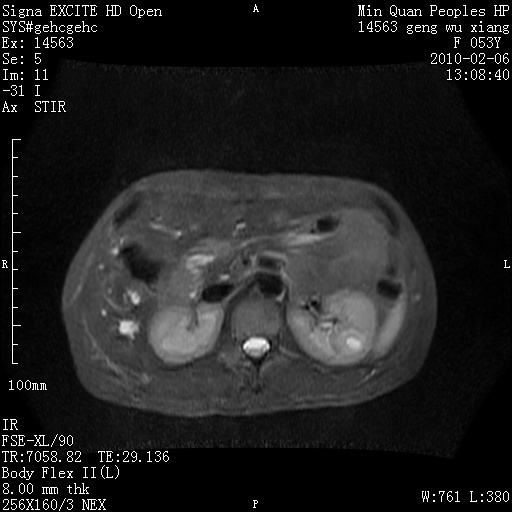

标题: MRI2762:胆道梗阻原因?

f,53y,全身黄染多日。

高位胆道梗阻 胆管癌可能性大

支持 高位胆道梗阻 胆管癌可能性大。